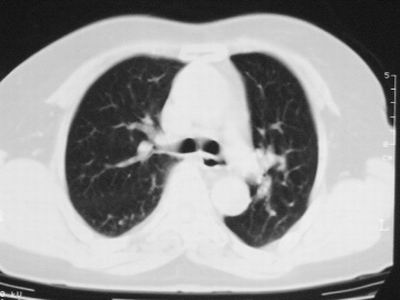

患者,女,64岁,4年前左腮腺"多形性"腺瘤手术治疗史.现复查胸部ct见左下肺块状影,该影与原左腮腺手术是否有联系?

表现:胸廓左右对称,气管居中,两肺野纹理增多,左下肺见一高密度影,周围见纤维条索影,心影及肺门无增大,双肋膈角锐利,横膈未见异常。

本次复查胸部ct

左下肺软组织块影,有分叶、毛刺、空泡及胸膜牵拉征,左下肺周围性肺癌。

左肺下叶周围型肺癌,支持!(软组织肿块+分叶+毛刺+空泡+胸膜凹陷征)

左下肺软组织密度影,可见分叶,边缘可见毛刺征,胸膜增厚,强烈要求左下肺周围型肺癌

左下肺后基底段实性肿块,周围有毛刺,病变周围有肺气肿,与降主动脉间有条带状影相连,病灶4年前查体发现,纵隔内未见肿大淋巴结。考虑.肺隔离症,建议增强扫描与周围型肺癌鉴别。